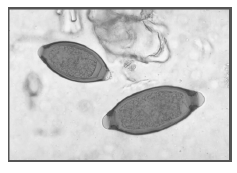

Observe a imagem de um exame parasitológico de fezes contendo ovos de um helminto e marque a alternativa correta quanto ao parasita em questão.